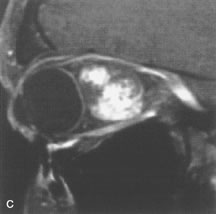

Cystic Lesions

Dermoid cysts appear as rounded, well-defined lesions typically contiguous with an orbital bony suture. The high-intensity signal on T1-weighted images is attributed to the sebaceous-produced lipid contents (Fig. 18).31,50 Mucoceles may demonstrate a hypointense or hyperintense signal on MR images, depending on the concentration of proteinaceous or inflammatory fluid components. The integrity of the bony walls of the expanded sinus cavities cannot be assessed on MR as well as by CT.37,50,55,56 A high-signal intensity on Tl- and T2-weighted images is characteristic of orbital chronic hematic cysts because of the blood-breakdown products within the cysts.57

Fig. 18. A. T1-weighted, (B) T2-weighted fat-suppressed, and (C) T1-weighted fat-suppressed MR scans demonstrate a small dermoid cyst arising near the palpebral portion of the lacrinal gland (arrows). The lesion is similar in signal intensity to fat on the T1-weighted scan (A) consistent with a high adipose tissue content. The lesion shows fat-suppression and low signal intensity on the two fat-suppressed sequences (B and C) confirming its high lipid content.